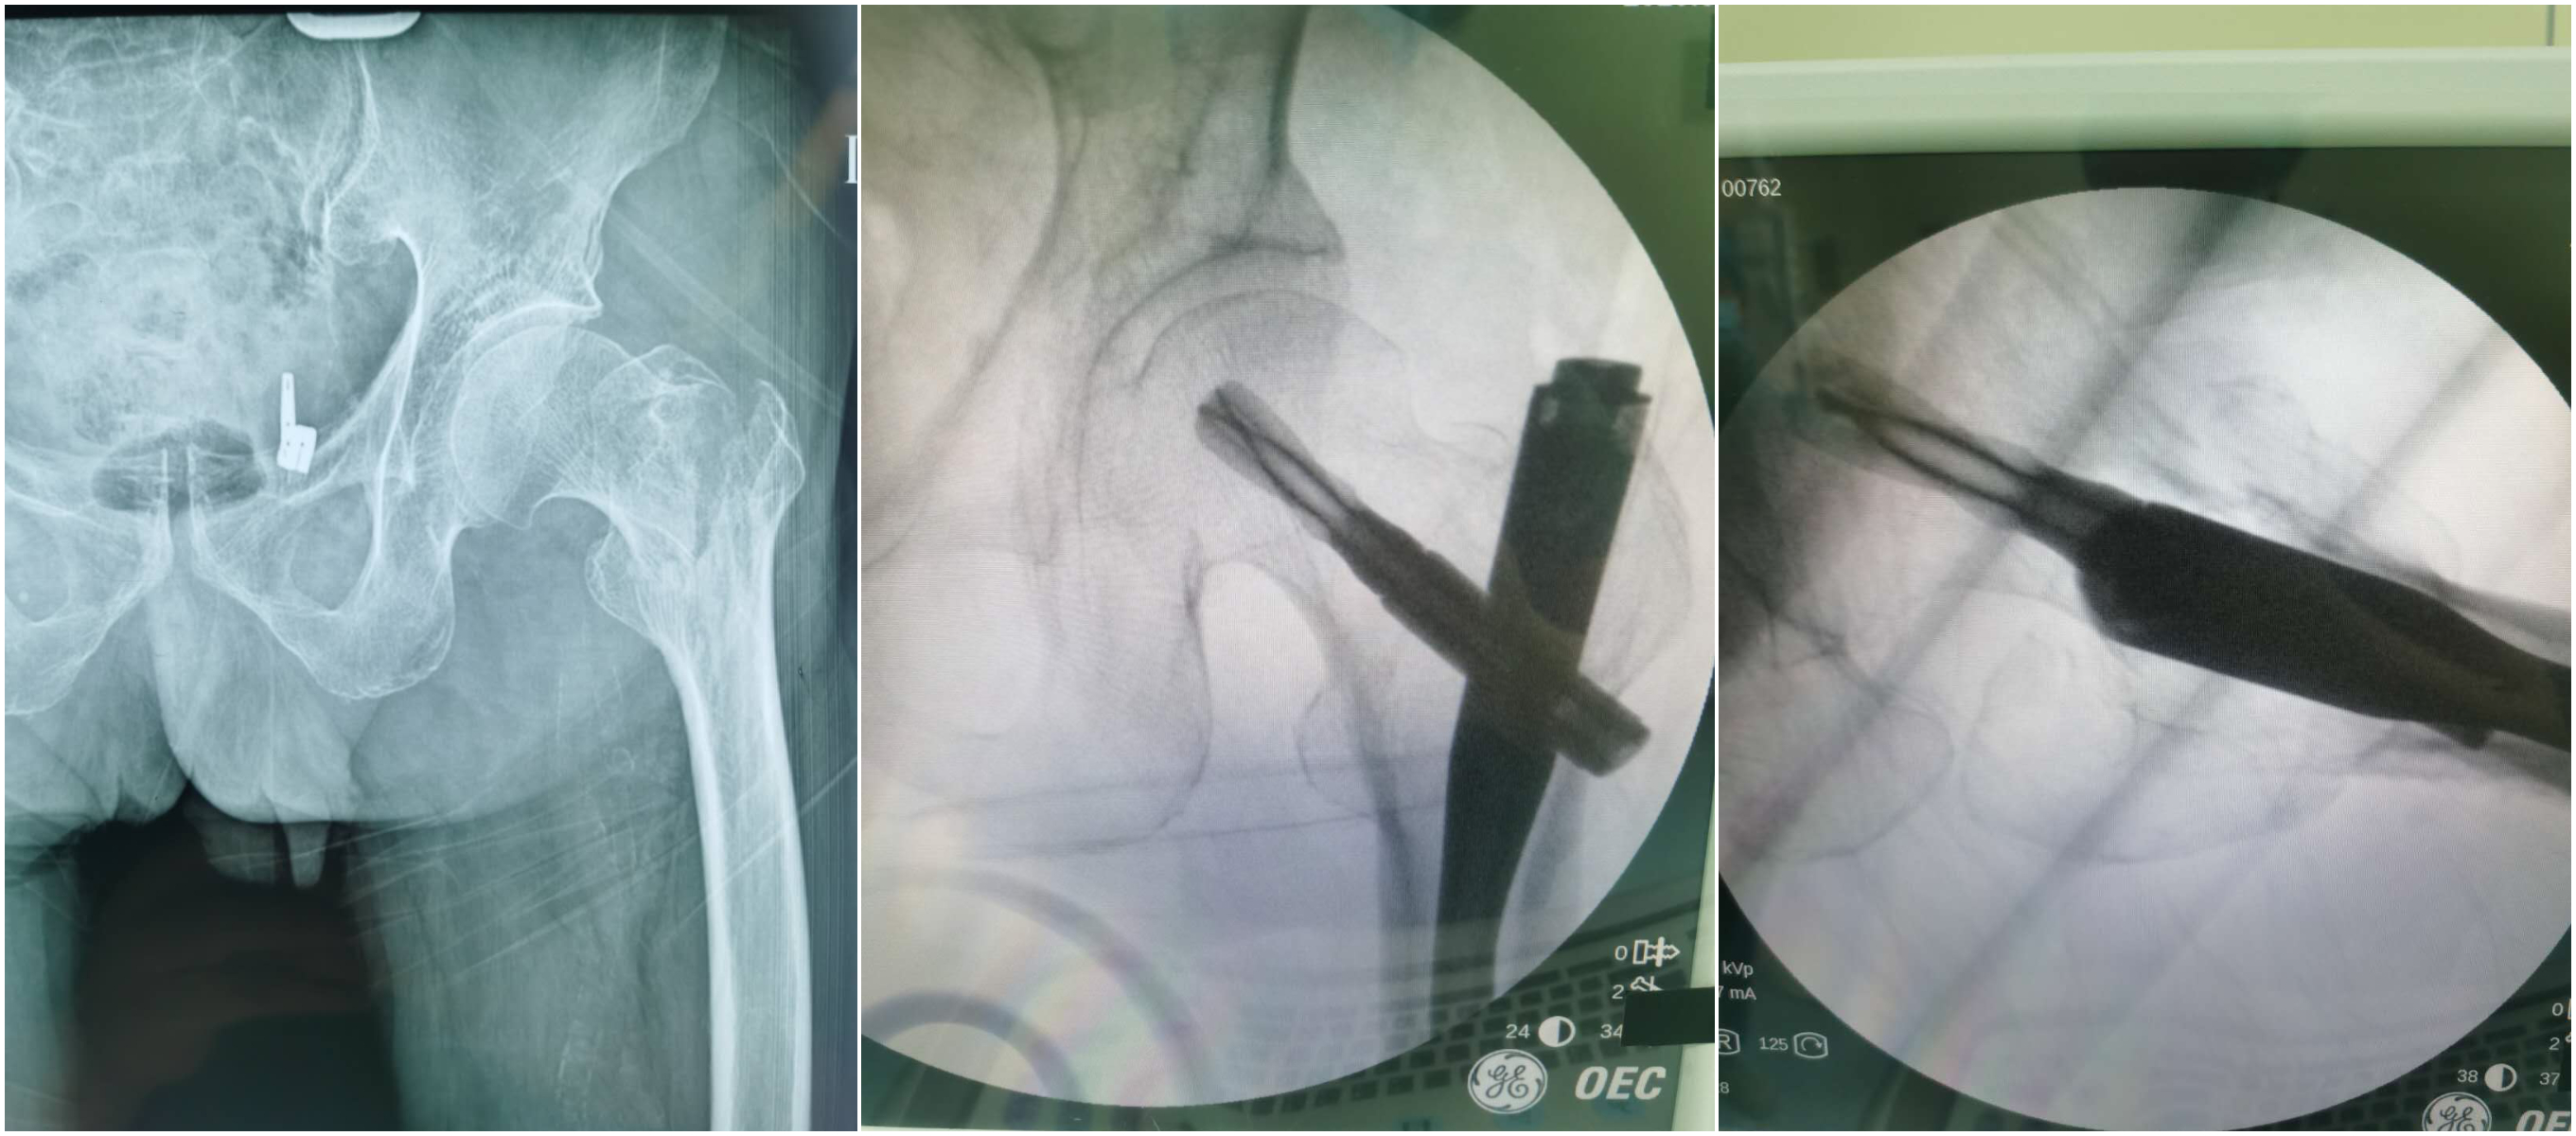

病例一:92岁,男性,粗隆间骨折,重度通气功能障碍,脱氧下血氧饱和度70%,吸氧状态下血氧饱和度88%。在麻醉科、呼吸科等相关科室同事的共同努力下安全进行了股骨粗隆间骨折闭合复位PFN内固定术。从开始手术到内固定放置完成一共用时18分钟。大大提高了手术安全性。术后3天出院。